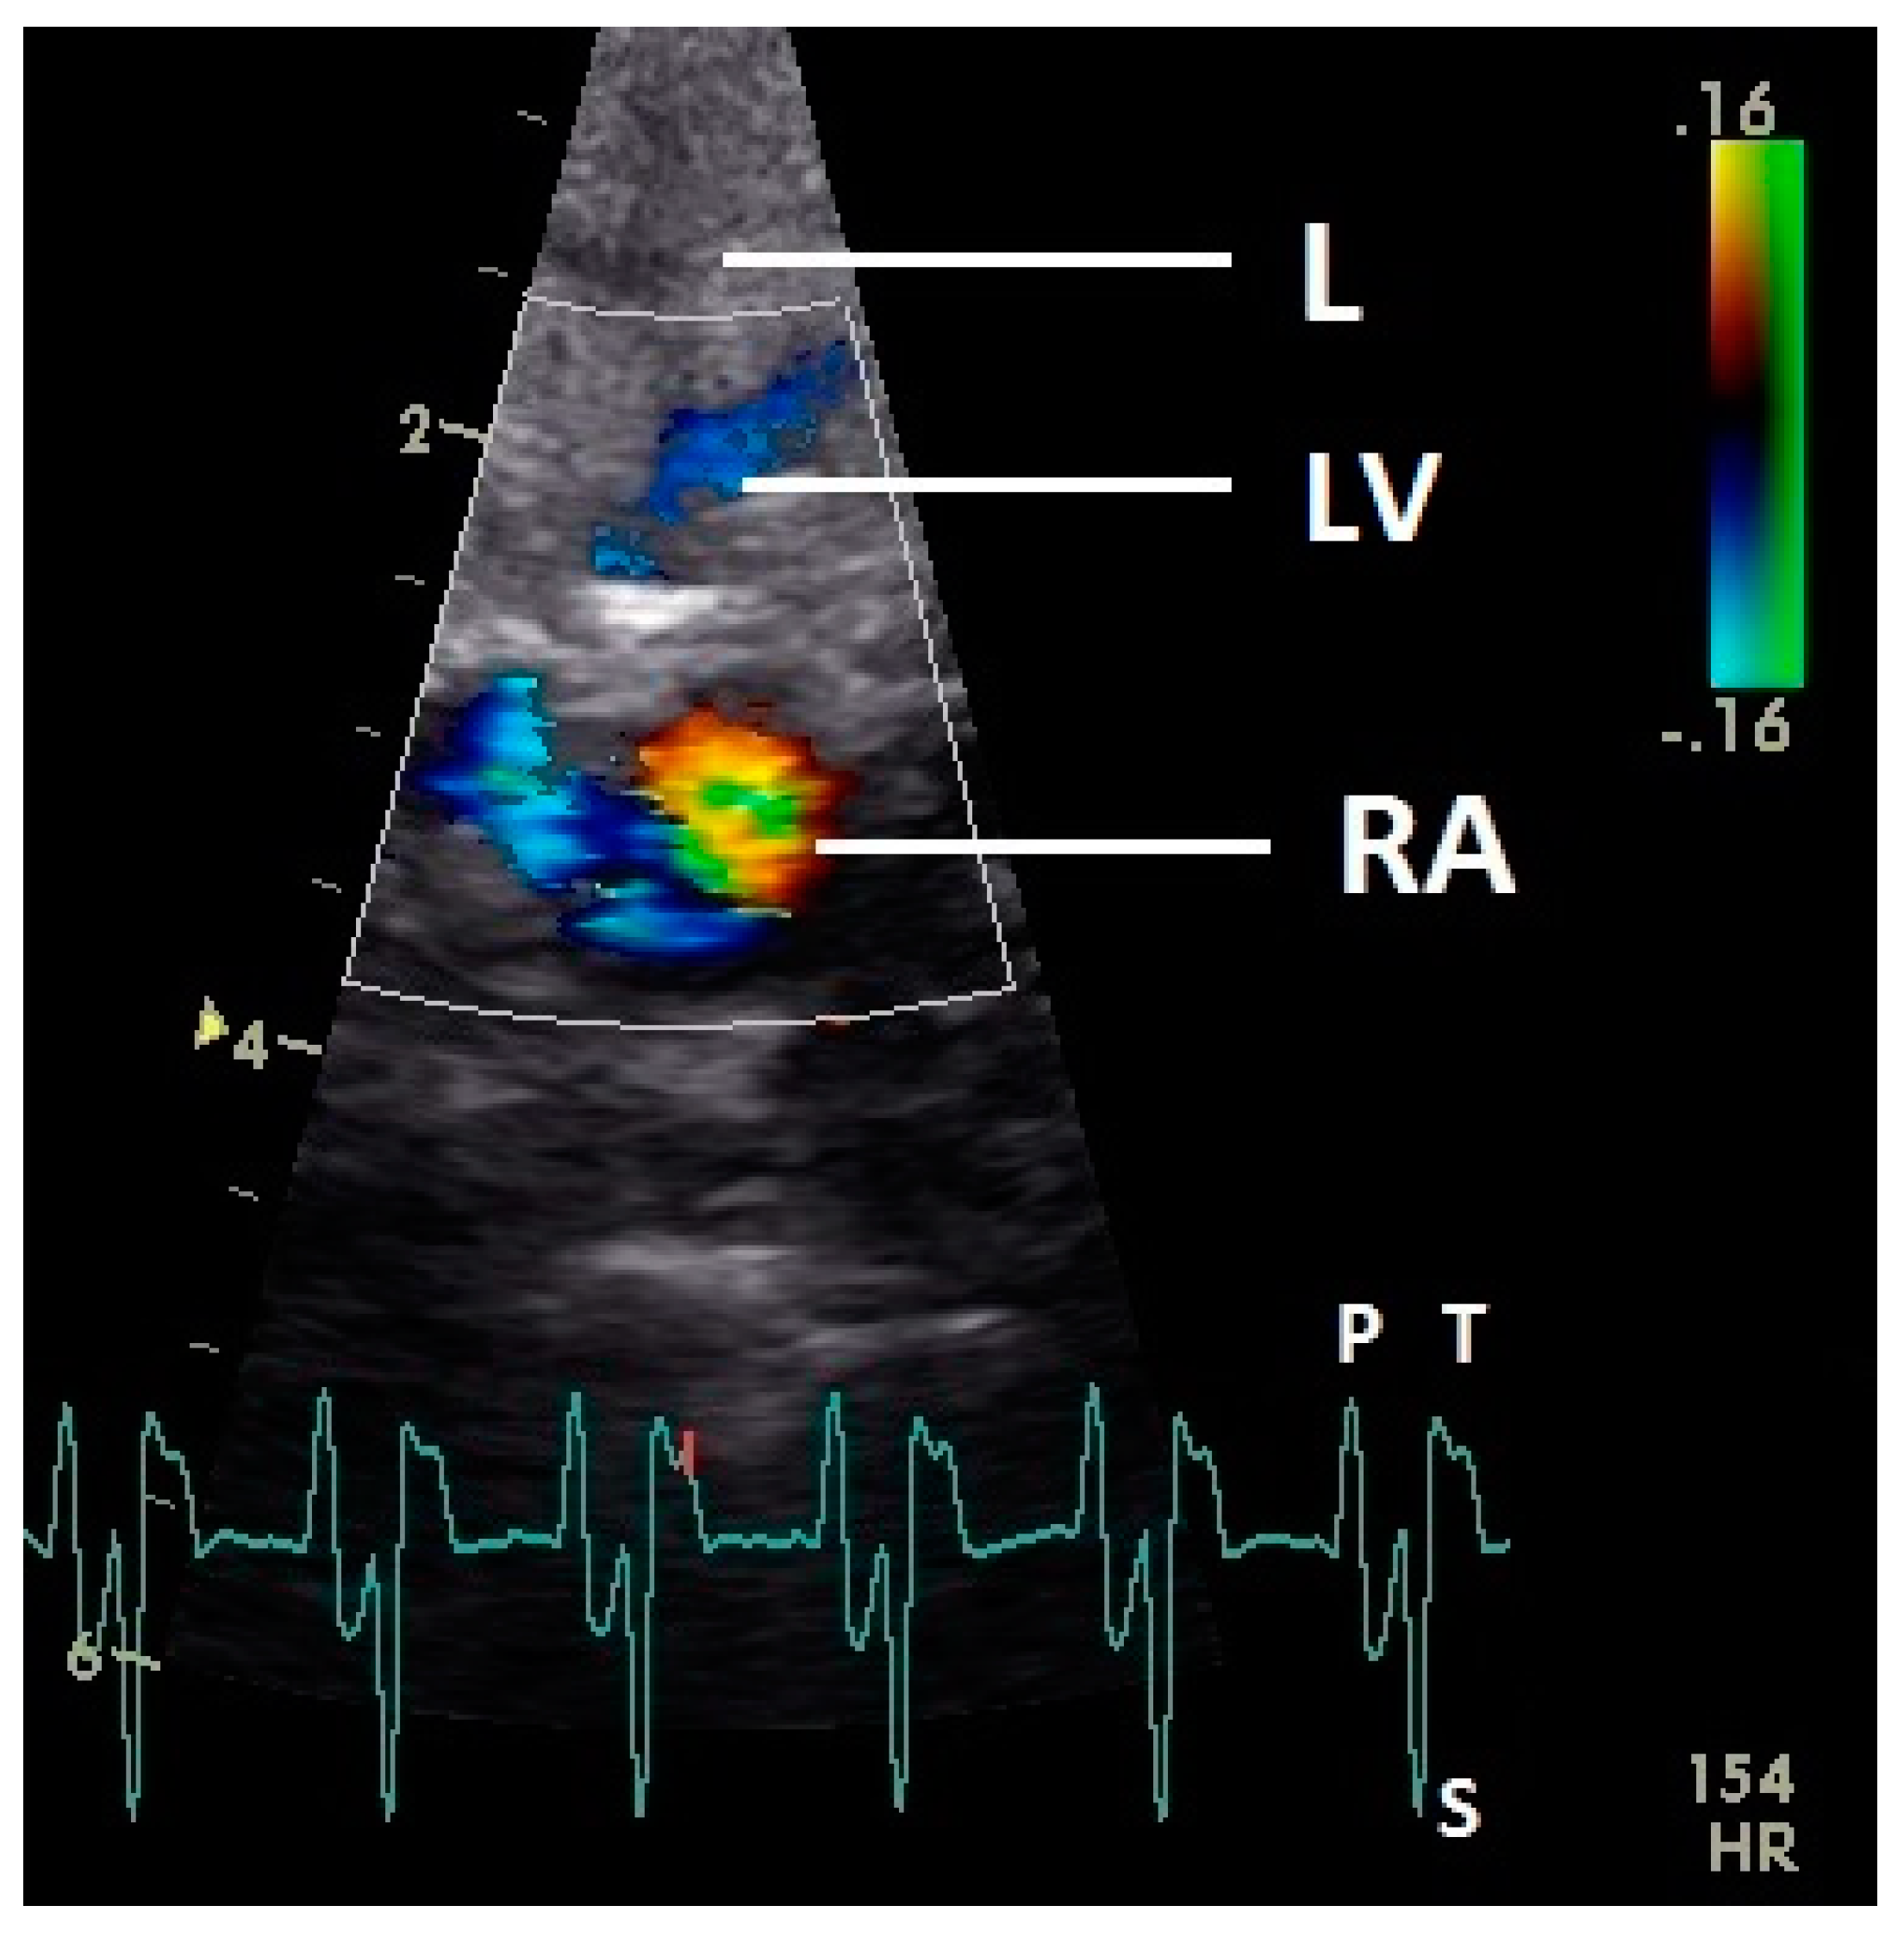

The early passive diastolic inflow in the right ventricle was visible as a red blood flow signal in 42 pigeons (97.7%; descending part of T wave in ECG). In four pigeons the passive diastolic inflow was connected with the active ventricular filling (EA wave). In the mid diastolic phase of the heart cycle no blood flow was recorded. During the active ventricular filling of the right ventricle (P wave of ECG) an intense red signal of high velocity was visible in all pigeons. In the active filling of the right ventricle, an intense blue signal behind the muscular right AV valve simultaneous to the larger red signal was detected in all pigeons (Figure 8). For some pigeons (25.6%) in this phase of the ventricular filling in the septal area of the blood inflow, a blue signal was also visible (p ≤ 0.001; Chi-squared test).

Figure 8.

Color Doppler image of the late active filling of the right ventricle. The blood inflow in the right ventricle from the atrium (red signal) and vortex formation of the blood flow behind the right muscular AV valve (blue signal) are visible. LV: left ventricle; LA: left atrium; RV: right ventricle; RA: right atrium; HR: heart rate. Electrocardiogram: P: P wave, S: S wave, T: T wave. The color scale on the right of the image is calibrated in m s−1.

The blood flow in the right atrium was observed in 35 pigeons and was difficult to examine with our settings. After the P wave of the ECG in the phase of the relaxation of the myocardium of the right atrium, a blue filling signal in 15 pigeons (34.9%) was visualized. In the second half of the systole (T wave) a late blue filling inflow signal in the atrium was seen in 35 pigeons (81.4%); at this time a blood flow in the liver veins was also observed (Figure 9). Simultaneously to the blue inflow signal a red blood flow signal in the area of the septum in the right atrium was observed (Figure 9).

Figure 9.

Color Doppler image of the late blood inflow in the right atrium (blue signal). The vortex formation of the blood flow in the atrium (red and blue signal simultaneously) and the blood flow in the liver vein (LV; blue signal in liver tissue) are visible. RV: right ventricle; RA: right atrium; HR: heart rate. Electrocardiogram: P: P wave, S: S wave, T: T wave. The color scale on the right of the image is calibrated in m s−1.